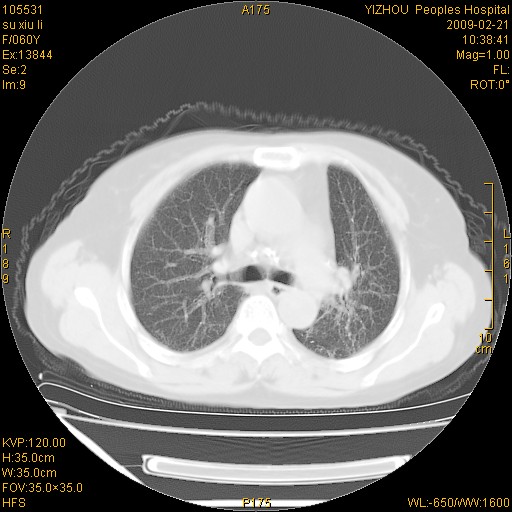

标题: CT18259:两肺间质纤维化?

女,60岁,反复咳嗽1月。

两肺支扩,以肺为著合并双肺较广范纤维化病变。建议除外结核等病变。

符合间质感染,部分纤维化表现

特发性间质纤维化

特发性间质纤维化伴支扩!